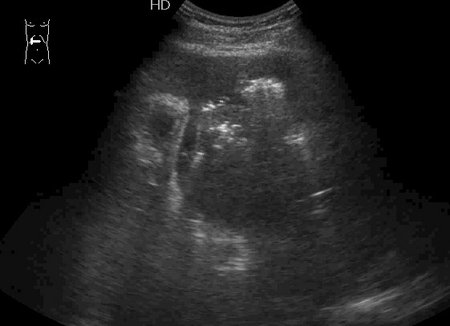

Типичная картина ##1-4:

Гипоэхогенное неоднородное округлое образование, окруженное эхогенным "демаркационным валом"

измененной паренхимы печени.

#5: Эмфизематозный абсцесс - в полости газ, экранирующий его содержимое.